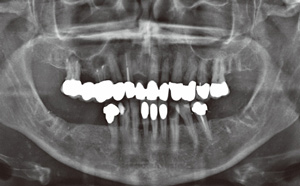

由于在2013 年10 月15 日的X 線檢查時(shí)已經(jīng)看到根管充填不足和根尖周骨質(zhì)溶解,因此在2013 年10 月21 日為16 和14 號(hào)牙齒行根尖切除術(shù)及倒充治療。另外,拔除27和37 號(hào)牙齒。隨后,拍攝了曲面斷層全景片(圖8)。修復(fù)性治療因33 和43 號(hào)牙齒計(jì)劃進(jìn)行全冠修復(fù),2013 年11 月5日由家庭牙醫(yī)進(jìn)行充填治療。此外,對(duì)根管充填不足的16和14 號(hào)牙齒重新根充,以用于上頜修復(fù)體的基牙。修復(fù)治療最早可在重新評(píng)估后再進(jìn)行,首先需要改善和穩(wěn)定牙周狀況。

圖8:2013 年10 月21 日術(shù)后曲面斷層全景X 線片(根尖切除和牙齒拔除)。